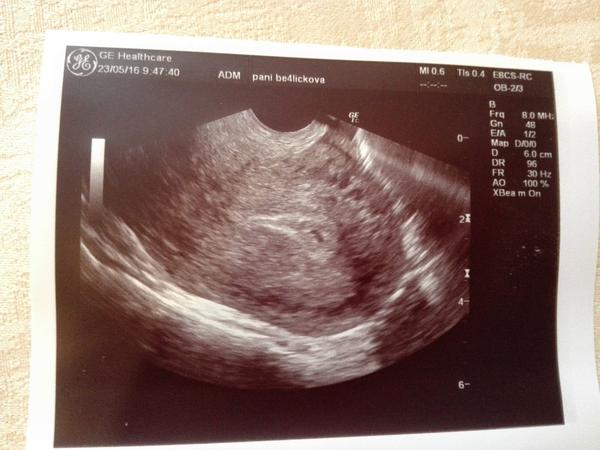

Tak jsem dnes byla na gynekologii, potvrdit tehu. S přítelem jsem sice krátce, ale plánovali jsme a netušili, že to vyjde 😉 dnes jsem byla týden po MS na gynde,nechala si potvrdit tehu. Fazolka tam je, akorát jsem se nezeptala, kolik tedy jsem. Da se to nějak spočítat doma? 😉 příkladem fotku, máme to pro pritelovi rodiče na víkend k narozeninam 😉

Tak jsem si to myslela dobře přesně 5tt😉

Počítá se podle poslední MS ale doktoři to berou podle UZ. Já jsem podle poslední MS v 18tt, dle UZ v 17tt a ten je důležitější. Příště se zeptej v kolikátém jsi, i když dr. by to mě říct sám.